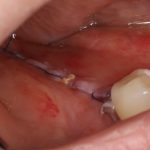

Вот клиническая картина через 4 месяца после ранее проведенной имплантации с остеопластикой:

Как видишь, коллеги из недалекой дружественной страны не осилили снятие швов. Мне это не нравится, хотя и объясняет, почему люди готовы ехать за тыщи километров ради 20-минутной операции удаления зуба мудрости.

Ну хорошо. Швы сняли. Делаем разрез. Обрати внимание, что после всех проведенных операций у нас остается очень небольшой по ширине слой жевательной слизистой оболочки:

Устанавливаем формирователи десневой манжеты. Сегодня я называю эту процедуру не менее важной, чем любой другой этап имплантологического лечения:

И швы. Просто швы. Никаких дополнительных процедур.

Если честно, то сейчас бы я использовал другой шовный материал и другой тип швов. Одно неизменно, — и я об этом много раз говорил, — самая широкая часть формирователя десны должна находиться на уровне десны. Так, чтобы эффективно отрабатывать т. н. «биологическую ширину».